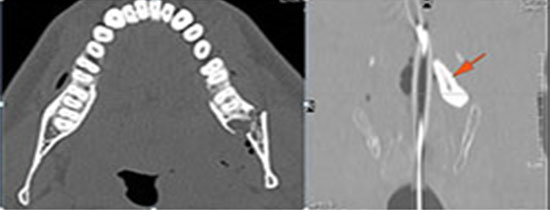

There is bony injury or displacement of the body, angle, ramus, parasymphyseal region, alveolar ridge, and condylar and coronoid process of the mandible. [In case of fracture, describe complexity and displacement]. [Yes/No]

The condylar head and fossa as well as the temporomandibular joint space are abnormal. [Yes/No]

There is condylar fracture either within or outside of the joint capsule, or with or without involvement of the articular surface of the condylar head. [Yes/No]

There is evidence of radiodense intra-articular osteochondral fragments. [Yes/No]

There is bony injury or displacement of the external auditory canal and/or other evidence of temporal bone injury. [Yes/No]

There are dental fractures and/or missing or displaced teeth. [Yes/No]